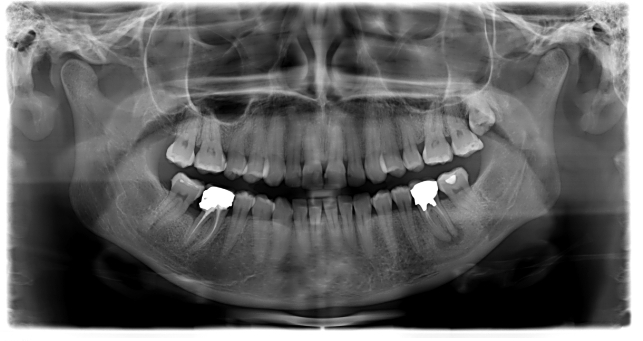

L’Ortopantomografia o Radiografia Panoramica delle Arcate Dentarie è un’indagine radiografica che utilizza i Raggi X.

L’indagine è eseguita mediante una apparecchiatura radiografica denominata Ortopantomografo con una tecnica radiografica denominata Tomografia ed evidenzia l’immagine delle Arcate Dentarie, dei Denti, delle Ossa Mascellari, della Mandibola, dei Seni Mascellari, del Canale del Nervo Mandibolare e delle Articolazioni Temporo-Mandibolari.

L’Ortopantomografia è utilizzata nell’ambito odontoiatrico e medico poichè permette di evidenziare patologie delle Arcate Dentarie, quali: Denti Inclusi, Cisti Mandibolari e Mascellari, Granulomi, Parodontopatie, Fratture dei Denti, fratture dei Mascellari; permette inoltre di evidenziare la presenza di tutti gli Elementi Dentari, la loro Forma e Posizione, la presenza di Carie Interdentale e di Carie al di sotto di otturazioni pregresse difficili da diagnosticare.